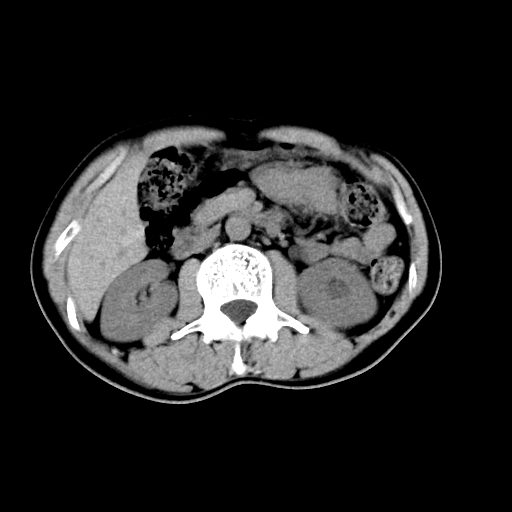

男,47岁,左输尿管结石碎石治疗后10余日。彩超示:左输尿管下段狭窄、输尿管积水。请各位讨论一下左输尿管下段结石还是静脉石?

两侧髂总动脉壁斑状及点状钙化.左侧输尿管行经与左髂总动脉相交后见高密度影,且下段输尿管管腔未见扩张,应该要考虑结石伴以上输尿管及肾盂积水.但右侧结节状高密度影,也应该是结石吧!那以上输尿管未见扩张呢!因此静脉结石可能性也较大.请问楼主碎石前左侧输尿管结石位置.

建议:把输尿管、膀胱扫全,除外输尿管下端结石,必要时强化或泌尿系造影除外其他.

左侧输尿管有轻度扩张伴有肾盂积水,输尿管下段周围的高密度影不象在输尿管内。

同意,不支持结石。(因显示该高密度影前见扩张输尿管影,另外两侧对称显示)。

左侧高密度影在左侧输尿管的内侧方,所以不考虑输尿管结石.

我认为不是结石的可能性大,因为他的位置和血管钙化的位置邻近